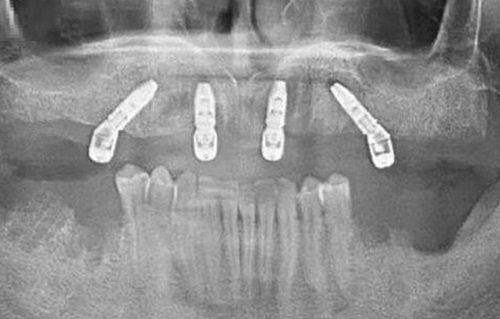

1. 种植牙项目

特别多人都关心新乡植得口腔医院的种植牙技术怎么样。其实,这里的种植牙技术相当不错。医院采用数字化种植牙技术,种出来的牙齿舒适美观,坚固耐用,几乎可以媲美真牙。在种植牙费用方面,价格透明规范,而且是亲民价格,能让大家用比较合理的价格种上优质好牙。比如说,对于单颗牙缺失的患者,医生会根据患者的口腔情况和经济状况,选择合适的种植体和牙冠,为患者制定个性化的种植方案。在临床应用中,已经有特别多患者通过种植牙修复了正常的咀嚼功能,对成效非常满意。